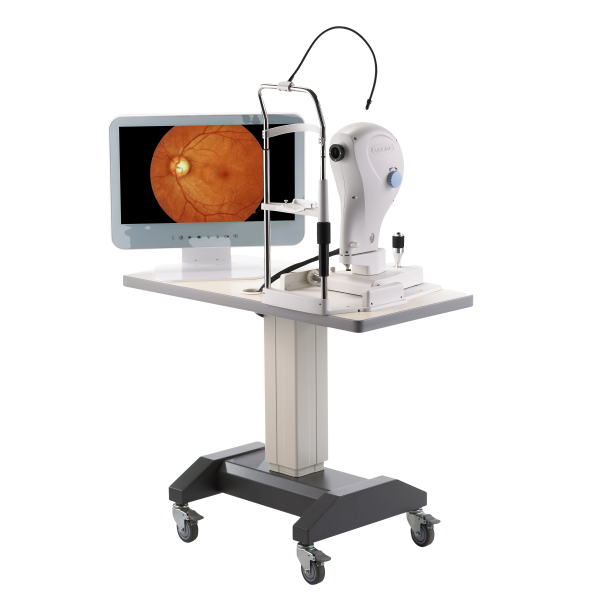

Инфракрасная Фундус Камера FundusVue Crystalvue

Инфракрасная Фундус Камера FundusVue быстрая и простая в использовании система визуализации сетчатки. FundusVue является вспомогательным инструментом, который помогает врачам в диагностике диабетической ретинопатии, возрастной дегенерации макулы, глаукомы и других заболеваниях сетчатки.

FundusVue обеспечивает немидриатическое цветное изображение дна глаза, это устройство является вспомогательным инструментом при диагностике заболеваний глаз. Фундус камера FundusVue, использует БИК-светодиоды в качестве подсветки при выравнивании сетчатки глаза пациента. Устройство обеспечивает только съемку изображений и никоим образом не предоставляет никаких диагностических или патологических анализов или заключений. FundusVue также не предназначен для использования в качестве единственного устройства диагностики, обнаружения и классификации заболеваний глаз.

Благодаря мягкой светодиодной подсветке и высокочувствительному ССD-сенсору FundusVue предлагает пациентам комфорт во время получения изображений сетчатки.